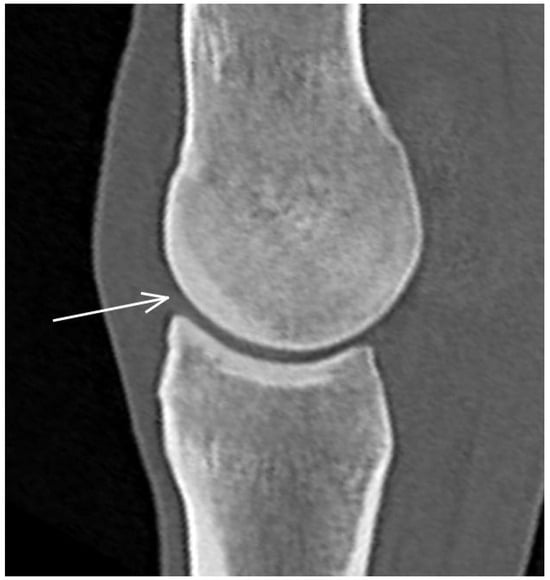

3.2. The Proximal Phalanx

| Proximal phalanx Sagittal groove | |||

| Subchondral bone thickening Dorsal/middle/palmar third Increased attenuation in the trabecular bone Hypoattenuating lesion in the subchondral bone Location | Subchondral bone thickening Dorsal/middle/palmar third Decreased signal intensity in the trabecular bone Increased signal intensity in the subchondral bone Location | Subchondral bone thickening Increased opacity in the trabecular bone Lucent lesion in the subchondral bone Location | |